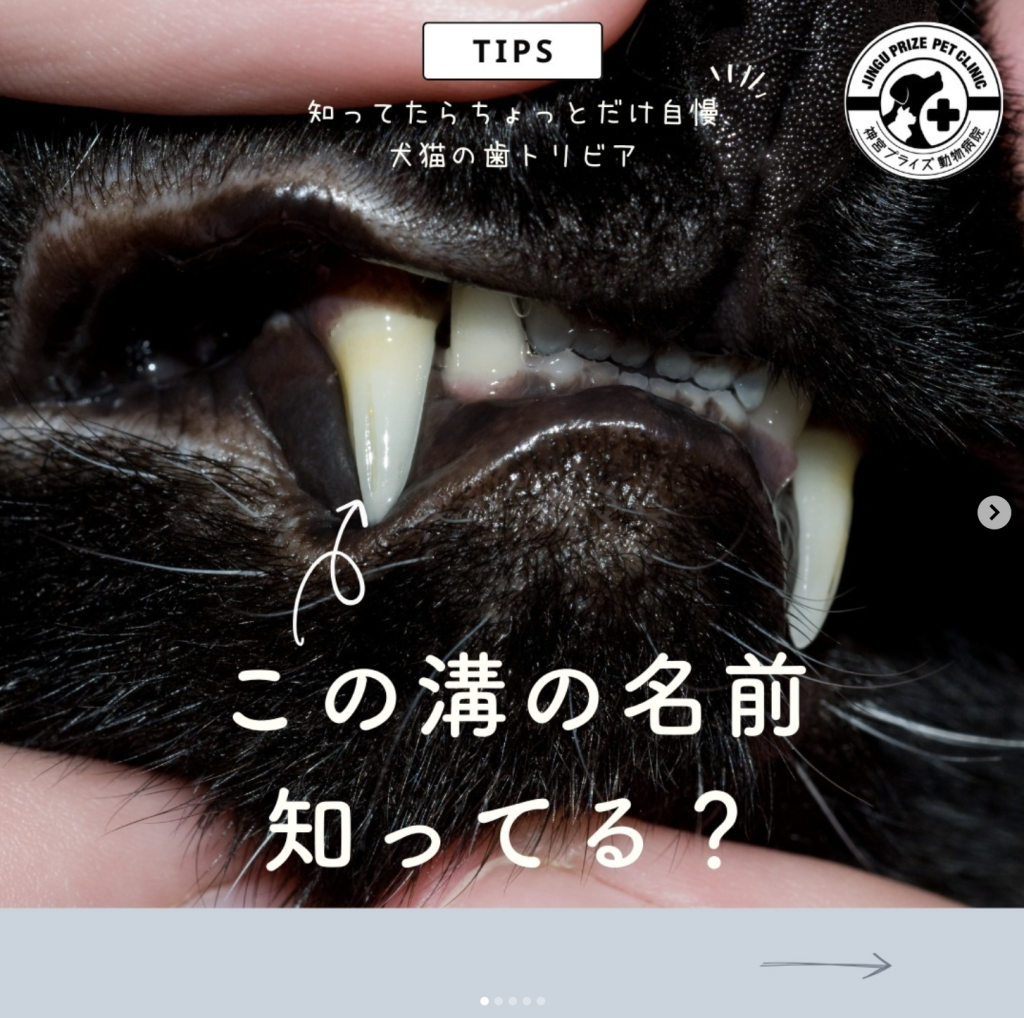

また、犬歯(牙)にはbleeding grooveと呼ばれる溝があり、この部位は捕食した獲物に噛み付いた際に血液を流出させるための構造と言われています。